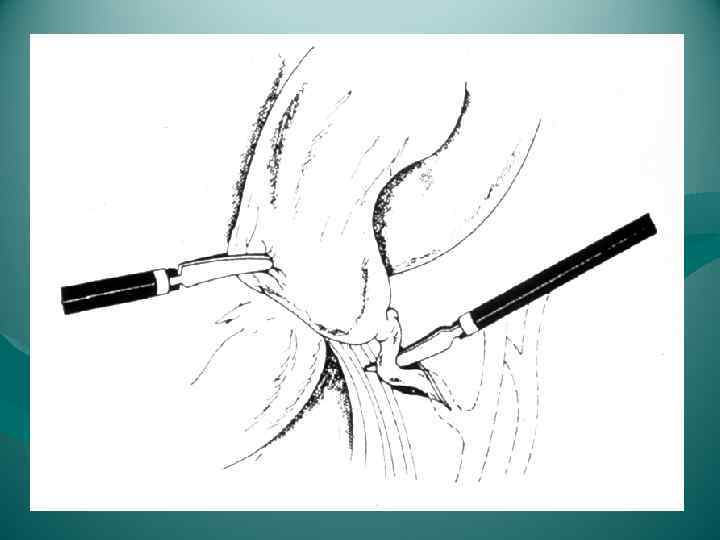

ЭТАПЫ ОПЕРАЦИИ ТИПИЧНОЙ ХОЛЕЦИСТЭКТОМИИ 1. Лапаротомия 2. Обнажение желчного пузыря 3. Выделение, перевязка и пересечение ductus cysticus и a. cystica 4. Выделение желчного пузыря из его ложа и удаление 5. Перитонизация ложа пузыря 6. Зашивание раны брюшной стенки ЭТАПЫ ОПЕРАЦИИ ЛАПАРОСКОПИЧЕСКОЙ ХОЛЕЦИСТЭКТОМИИ 1. Оперативный доступ 2. Выделение желчного пузыря из сращений с окружающими тканями 3. Выделение, клипирование и пересечение пузырного протока и пузырной артерии 4. Отделение желчного пузыря от печени 5. Извлечение желчного пузыря из брюшной полости

ЭТАПЫ ОПЕРАЦИИ ТИПИЧНОЙ ХОЛЕЦИСТЭКТОМИИ 1. Лапаротомия 2. Обнажение желчного пузыря 3. Выделение, перевязка и пересечение ductus cysticus и a. cystica 4. Выделение желчного пузыря из его ложа и удаление 5. Перитонизация ложа пузыря 6. Зашивание раны брюшной стенки ЭТАПЫ ОПЕРАЦИИ ЛАПАРОСКОПИЧЕСКОЙ ХОЛЕЦИСТЭКТОМИИ 1. Оперативный доступ 2. Выделение желчного пузыря из сращений с окружающими тканями 3. Выделение, клипирование и пересечение пузырного протока и пузырной артерии 4. Отделение желчного пузыря от печени 5. Извлечение желчного пузыря из брюшной полости

ЭТАПЫ ЛАПАРОСКОПИЧЕСКОЙ ХОЛЕЦИСТЭКТОМИИ 1. Оперативный доступ 2. Выделение желчного пузыря из сращений с окружающими тканями 3. Выделение, клипирование и пересечение пузырного протока и пузырной артерии 4. Отделение желчного пузыря от печени 5. Извлечение желчного пузыря из брюшной полости

ЭТАПЫ ЛАПАРОСКОПИЧЕСКОЙ ХОЛЕЦИСТЭКТОМИИ 1. Оперативный доступ 2. Выделение желчного пузыря из сращений с окружающими тканями 3. Выделение, клипирование и пересечение пузырного протока и пузырной артерии 4. Отделение желчного пузыря от печени 5. Извлечение желчного пузыря из брюшной полости